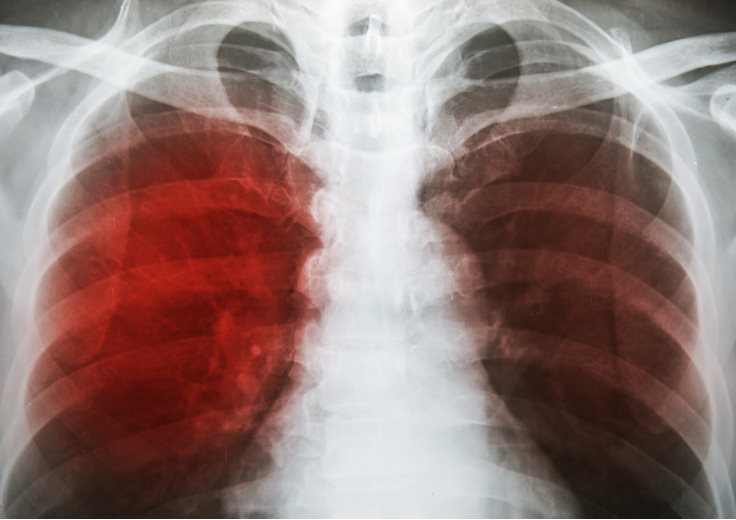

• Lower Respiratory Infections: 3.19 million deaths per year.[5]

• Lung Disease

Lower respiratory infections include a range of illnesses such as pneumonia, bronchitis, and edema. Symptoms include fever, difficulty breathing, and fatigue. These infections pose great risks to the elderly or those with weakened immune systems.

• Chronic Obstructive Pulmonary Disease: 3.17 million deaths per year.[5]

• Death Causes COPD

Chronic Obstructive Pulmonary Disease can be caused or exacerbated by smoking. This disease, whose two main forms are chronic bronchitis and emphysema, makes it difficult to breathe deeply and can lead to a weakening of the lungs and eventual death.